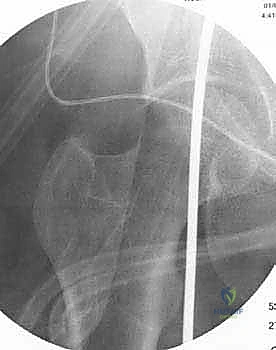

3. إجراء القطع العظمي (The Osteotomy):

باستخدام أدوات دقيقة ومناشير جراحية متطورة، يتم عمل قطع غير مكتمل في عظمة الساق. هناك طريقتان رئيسيتان:

4. تعديل المحور:

يتم فتح العظم تدريجياً وببطء شديد حتى الوصول إلى الزاوية التي تم حسابها في التخطيط الرقمي قبل الجراحة.